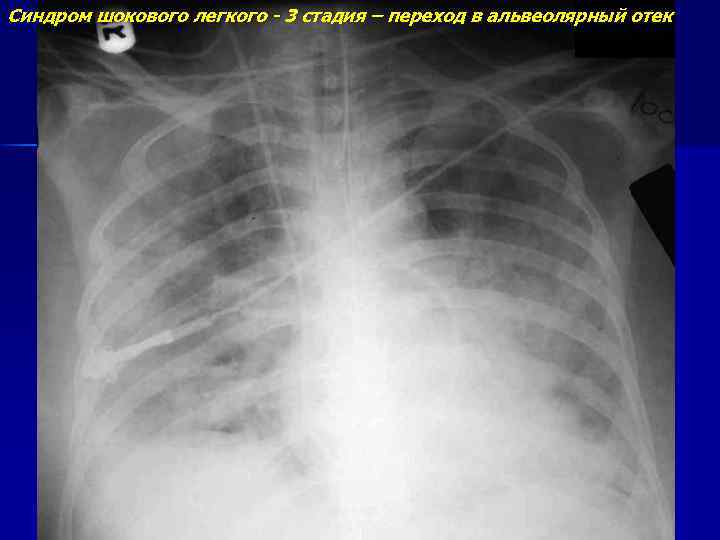

Синдром шокового легкого - 3 стадия – переход в альвеолярный отек